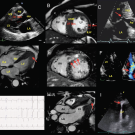

Danon Disease

03/10/2017

Howard K. Song, MD, PhD; Suwen Kumar, MD; Meghan Chirpich, MS, CGC; Stephen Heitner, MD

Hypertrophic cardiomyopathy is a phenotypically heterogeneous cardiac condition with a multitude of physiologic effects.